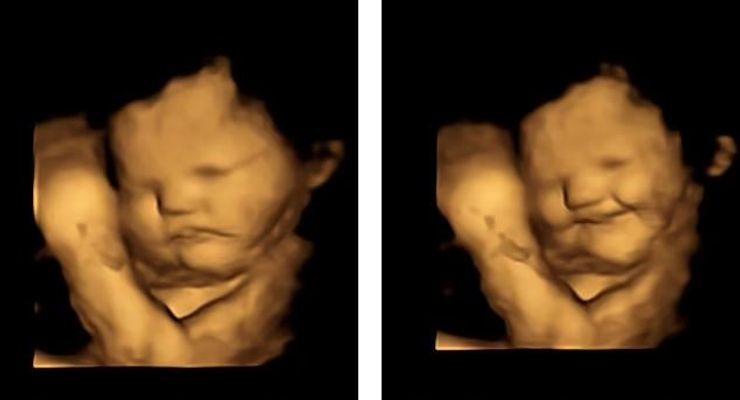

Реакція малих на моркву.

Реакція малих на моркву

Так, у 100% випадків малюки мам, які отримали капсулу з броколі, кривилися та хмурилися. Водночас малюки, чиї мами з'їли моркву, виглядали щасливими та усміхненими. Отримані результати, на думку вчених, свідчать про те, що харчові звички починають формуватися ще в утробі матері, коли ми вперше "пробуємо" ті чи інші смаки.